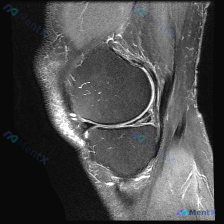

给大家分享一个很有启发的膝关节MRI读片病例,临床关注点是半月板异常,读完片发现其实核心问题不在这儿,整理一下完整分析思路。 病例影像基本信息 这是一份膝关节矢状位T2加权MRI(压脂序列),我们先整理所有客观发现: 1. 关节内结构:半月板形态完整,呈典型低信号三角表现,未见贯穿性高信号,边缘光滑...